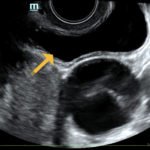

The ultrasound video clip demonstrates a transverse view of the pelvis using the endocavitary probe. The bladder can be seen on the anterior portion of the scan (yellow arrow), while the uterus with an intrauterine pregnancy is visible posteriorly (blue arrow). The thickened appearance of the uterine wall is also indicative of pregnancy. A large, anechoic cystic structure measuring approximately 5 cm is seen in the vicinity of the patient’s left adnexa (pink arrow), which raises concerns for ovarian torsion.1

Based on the clinical presentation and the bedside ultrasound, obstetrician-gynecologist (OB/gyn) was emergently consulted and the patient was transferred to the operating room (OR) where she was found to have a paratubal cyst in the left fallopian tube with associated isolated tubal torsion. After manually de-torsing the tube, which was initially dilated and dusky, blood flow was restored and the color returned to normal. A cystectomy was performed without complications. The patient was discharged later that day after the follow-up ultrasound showed reassuring fetal heart tones and good blood flow to the left ovary.

When using bedside ultrasound, the most reliable indicator of ovarian torsion is an enlarged ovary, greater than 4 cm in size.3In addition to looking for an enlarged ovary, additional sonographic findings that can be indicative of torsion include a solid, cystic, or complex mass, with or without fluid, or cystic hemorrhage.4 Ovarian cysts are risk factors due to their capacity to serve as pivot points for ovaries to twist around.1,4 When performing the ultrasound, it is possible to see little or no intra-ovarian venous flow or absent arterial flow, but because there is dual blood supply to the ovaries from the ovarian and uterine arteries, normal vascularity does not exclude torsion.